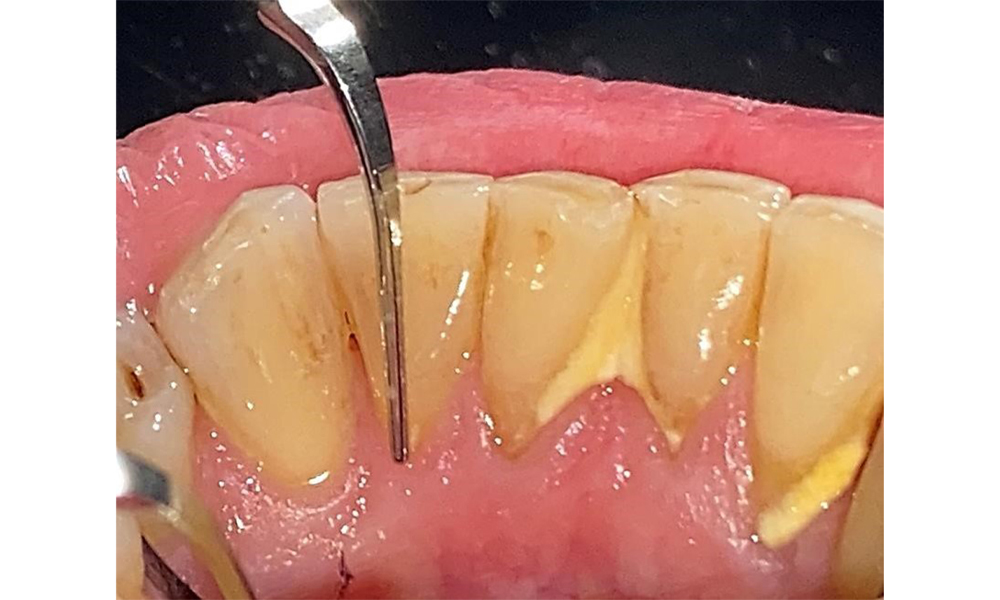

The patient has stage II, grade B periodontitis (5). At 1 to 3 mm, the clinical probing depths were within the physiological range. Localized probing depths of 5 mm were observed on the mesiopalatal aspects on both 17 and 27. There are generalized recessions of 1–3 mm with partial loss of the interdental papillae (Fig. 2, Fig. 3, Fig. 4)

The patient uses interdental brushes and an electric toothbrush. This demonstrates good compliance and good intraoral hygiene behaviour and understanding at home. Regular motivation and re-instruction are indispensable due to the risk of progression, particularly with regard to the cleaning of interdental areas, since increased probing depths were detected in these areas. Localized calculus and soft plaque was present in the lingual anterior mandibular region, and these must be shown to the patient. The interdental brush size may need to be checked and adjusted. A soft brush attachment is recommended based on the presence of exposed root surfaces to prevent wedge-shaped defects. Toothpaste with a low abrasive value should be used.